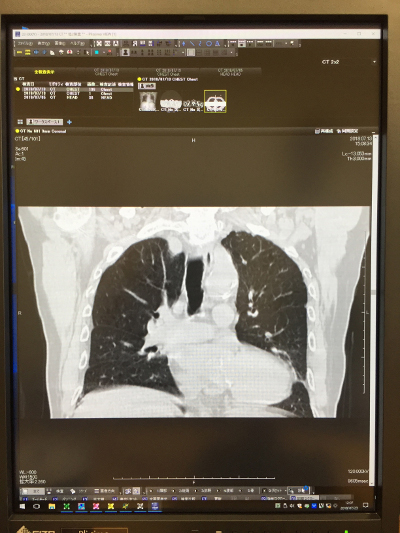

CT<胸部>